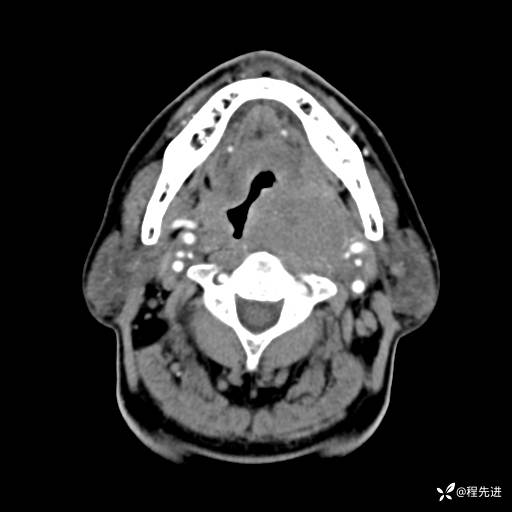

CT增强:

静脉期: